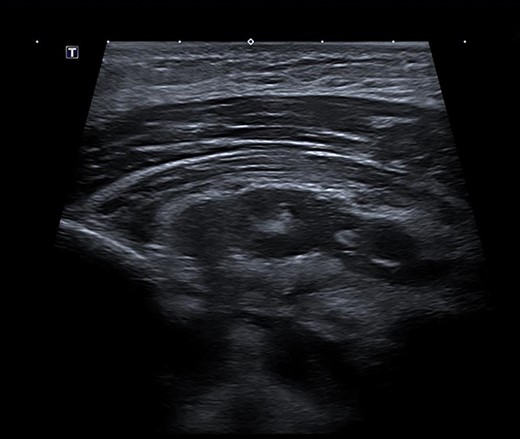

The patient was commenced on a regimen of intravenous flucloxacillin and clindamycin. Blood cultures subsequently grew methicillin-sensitive S. aureus. Despite antibiotics, his symptoms worsened. His neutrophils and CRP increased to 16 000 cells/μL and 404 mg/L, respectively. Repeat MRI scan on day 5 showed further progression of myositis with new rim-enhancing collections within the left supero-medial pectoralis major muscle extending inferiorly and posteriorly to the first rib sternal articulation. The collection also extended through the left first rib sternal articulation into the anterosuperior mediastinum (Fig. 2b). Furthermore, there was now compression of the left brachiocephalic vein.

(A) Post-contrast MRI scan showing areas enhancement around pectoralis major (myositis) with extension into the mediastinum (mediastinitis) (white arrows). (B) New rim-enhancing collections within left pectoralis major muscle. The collection appears to extend posteriorly into the anterosuperior mediastinum (white arrows)